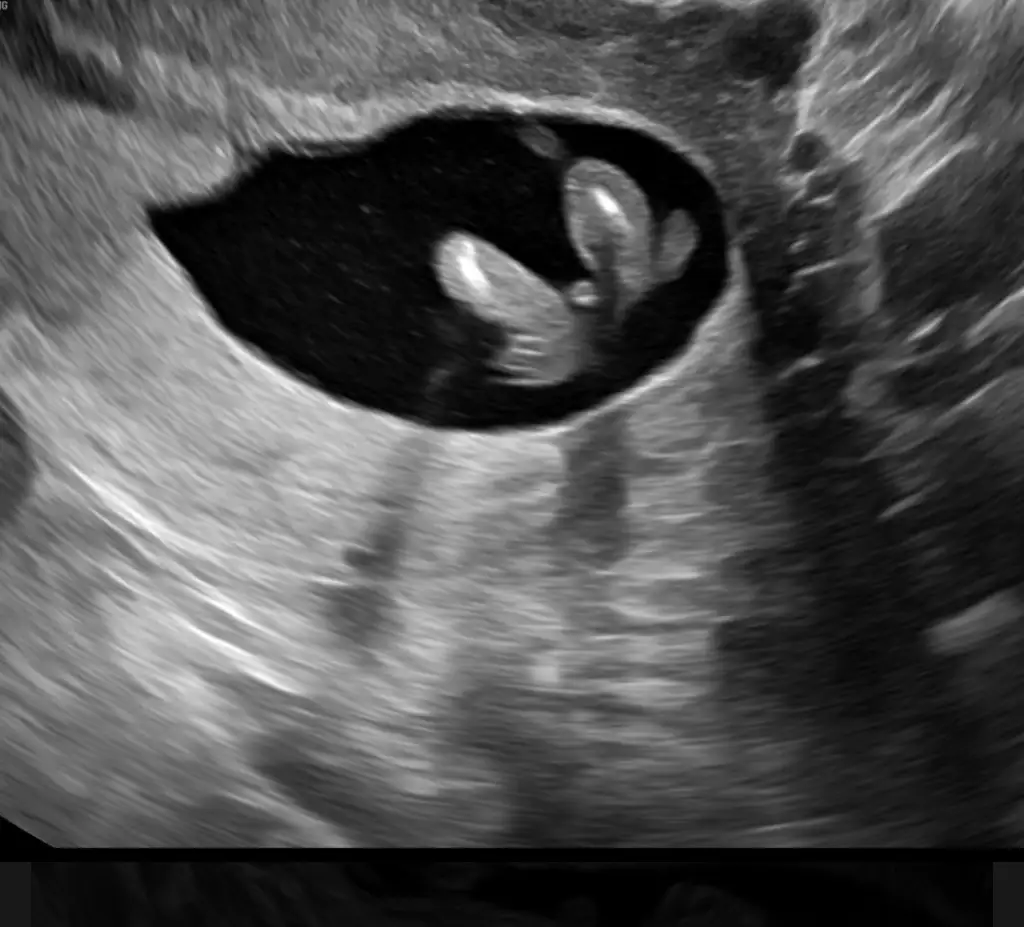

Merhaba bana bi tahminde bulunabilir misiniz Dr kıza benzetti 🫠❤️

• IMG_8284.webp